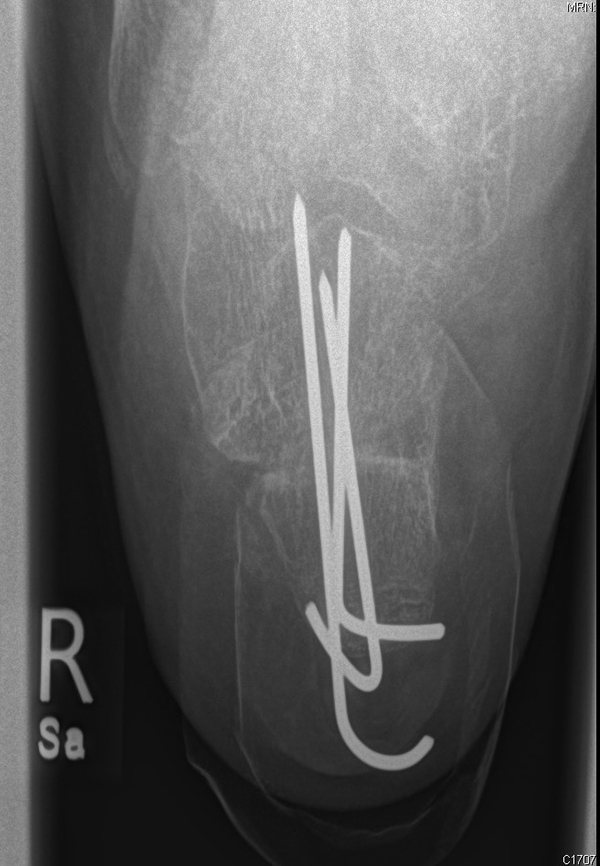

Liegt eine stark subduktische 5. Zehenposition vor, fräsen wir bevorzugt in der Kramertechnik für eine maximale Korrektur und Setzen für zwei bis drei Wochen einen intramedullären Draht nach proximal durch die Osteotomie (Abb. 27).

Abb. 27 a-d: Radiologische Darstellung intraoperativ (a) und vor dem Entfernen des Drahtes einer kompletten Schaftosteotomie mit intramedullärem Draht stabilisiert (b). Die Osteotomie wird minimalinvasiv durchgeführt und der Draht nach der Spülung über den gleichen Hautschnitt einfach in den Schaft hineingeschoben und die Osteotomie darüber stabilisiert. Das Köpfchen kann anschließend je nach Bedarf plantarisiert oder extendiert werden. Radiologische Verlaufskontrolle vor Entfernung des Drahtes (c-d).